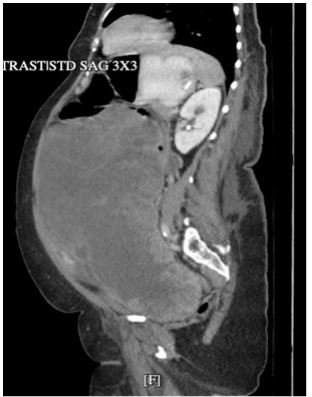

Figure 1: Pre-operative computerized tomography image of the abdomen and pelvis with IV contrast.

Computed Tomography of the Abdomen and Pelvis (CTAP) with intravenous contrast demonstrated a 22.6×28.9×16 cm heterogeneous pelvic mass with both solid and cystic components, concerning for an ovarian or uterine neoplasm.

Associated findings included moderate bilateral hydroureteronephrosis and bladder compression, likely secondary to the mass effect (Figure 1).